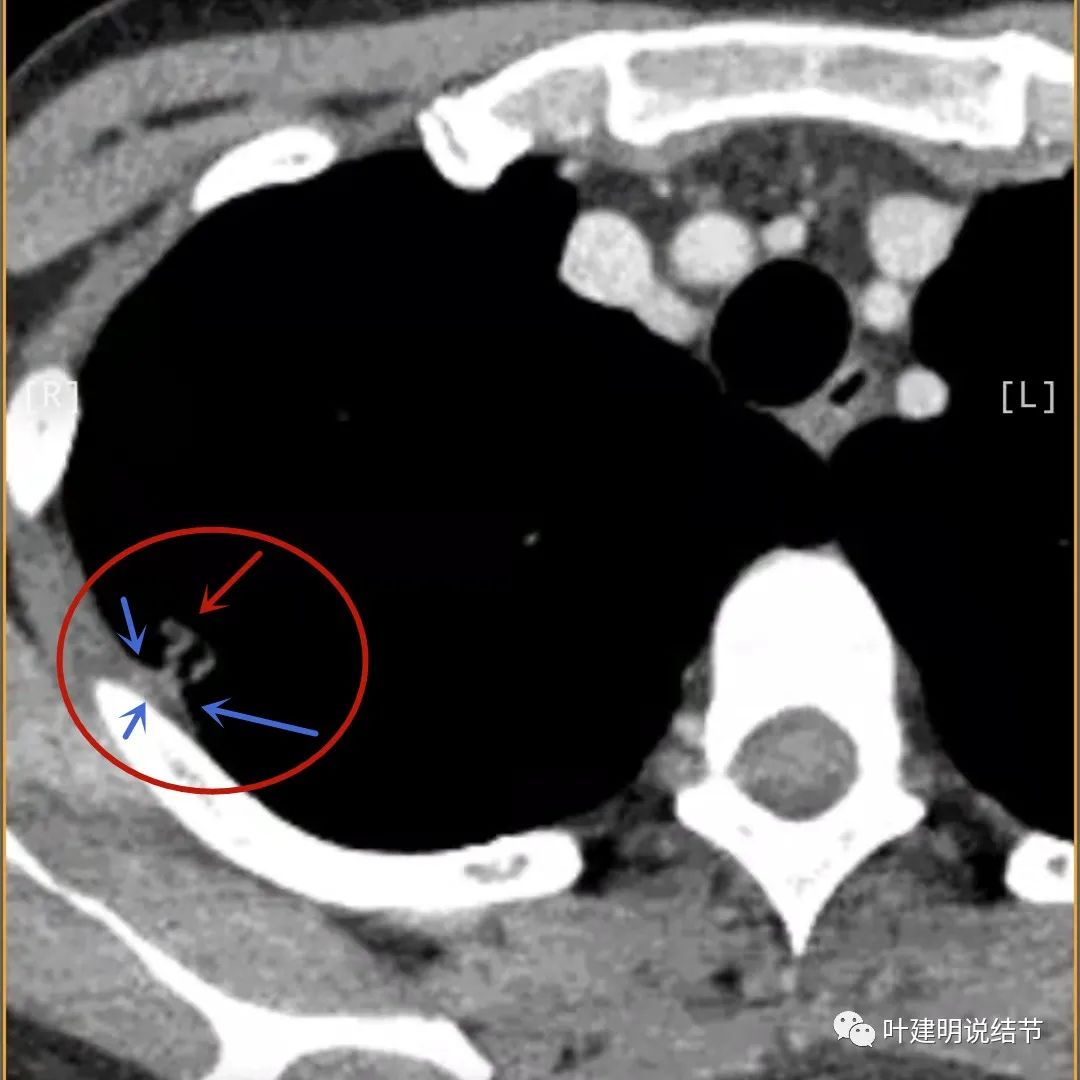

病灶有明显强化(说明炎性可能性大,如果恶性这样强化,血供丰富,应该倍增速度更快。蓝色箭头示胸膜处低于软组织密度的区域;桔色箭头示病灶边缘平直缺乏膨胀性;黄色箭头示中间的空腔

邻近胸膜处的增厚密度低于肌肉组织,病灶强化明显且均匀

天蓝色箭头示病灶低密度区,考虑坏死可能性大,桔色箭头示边缘凹陷无膨胀性

上图示空洞偏心,而且红色箭头所指处与空腔似乎是整合,而非囊壁生长增厚。天蓝色箭头示近胸膜处的低密度区域,考虑坏死成分,囊壁的邻近部分也是极低密度区域,也可能是干酪样坏死区

薄层影像印象:病灶有明显强化,且邻近胸膜处及部分囊壁区有极低密度区域,考虑干酪样坏死可能性大,肿瘤的坏死可能性小,肿瘤一般要长的比较大,中央缺血性坏死。整体病灶也是觉得散,且邻近胸膜处甚厚。考虑炎性,尤其是肉芽肿性炎伴干酪样坏死可能性大。